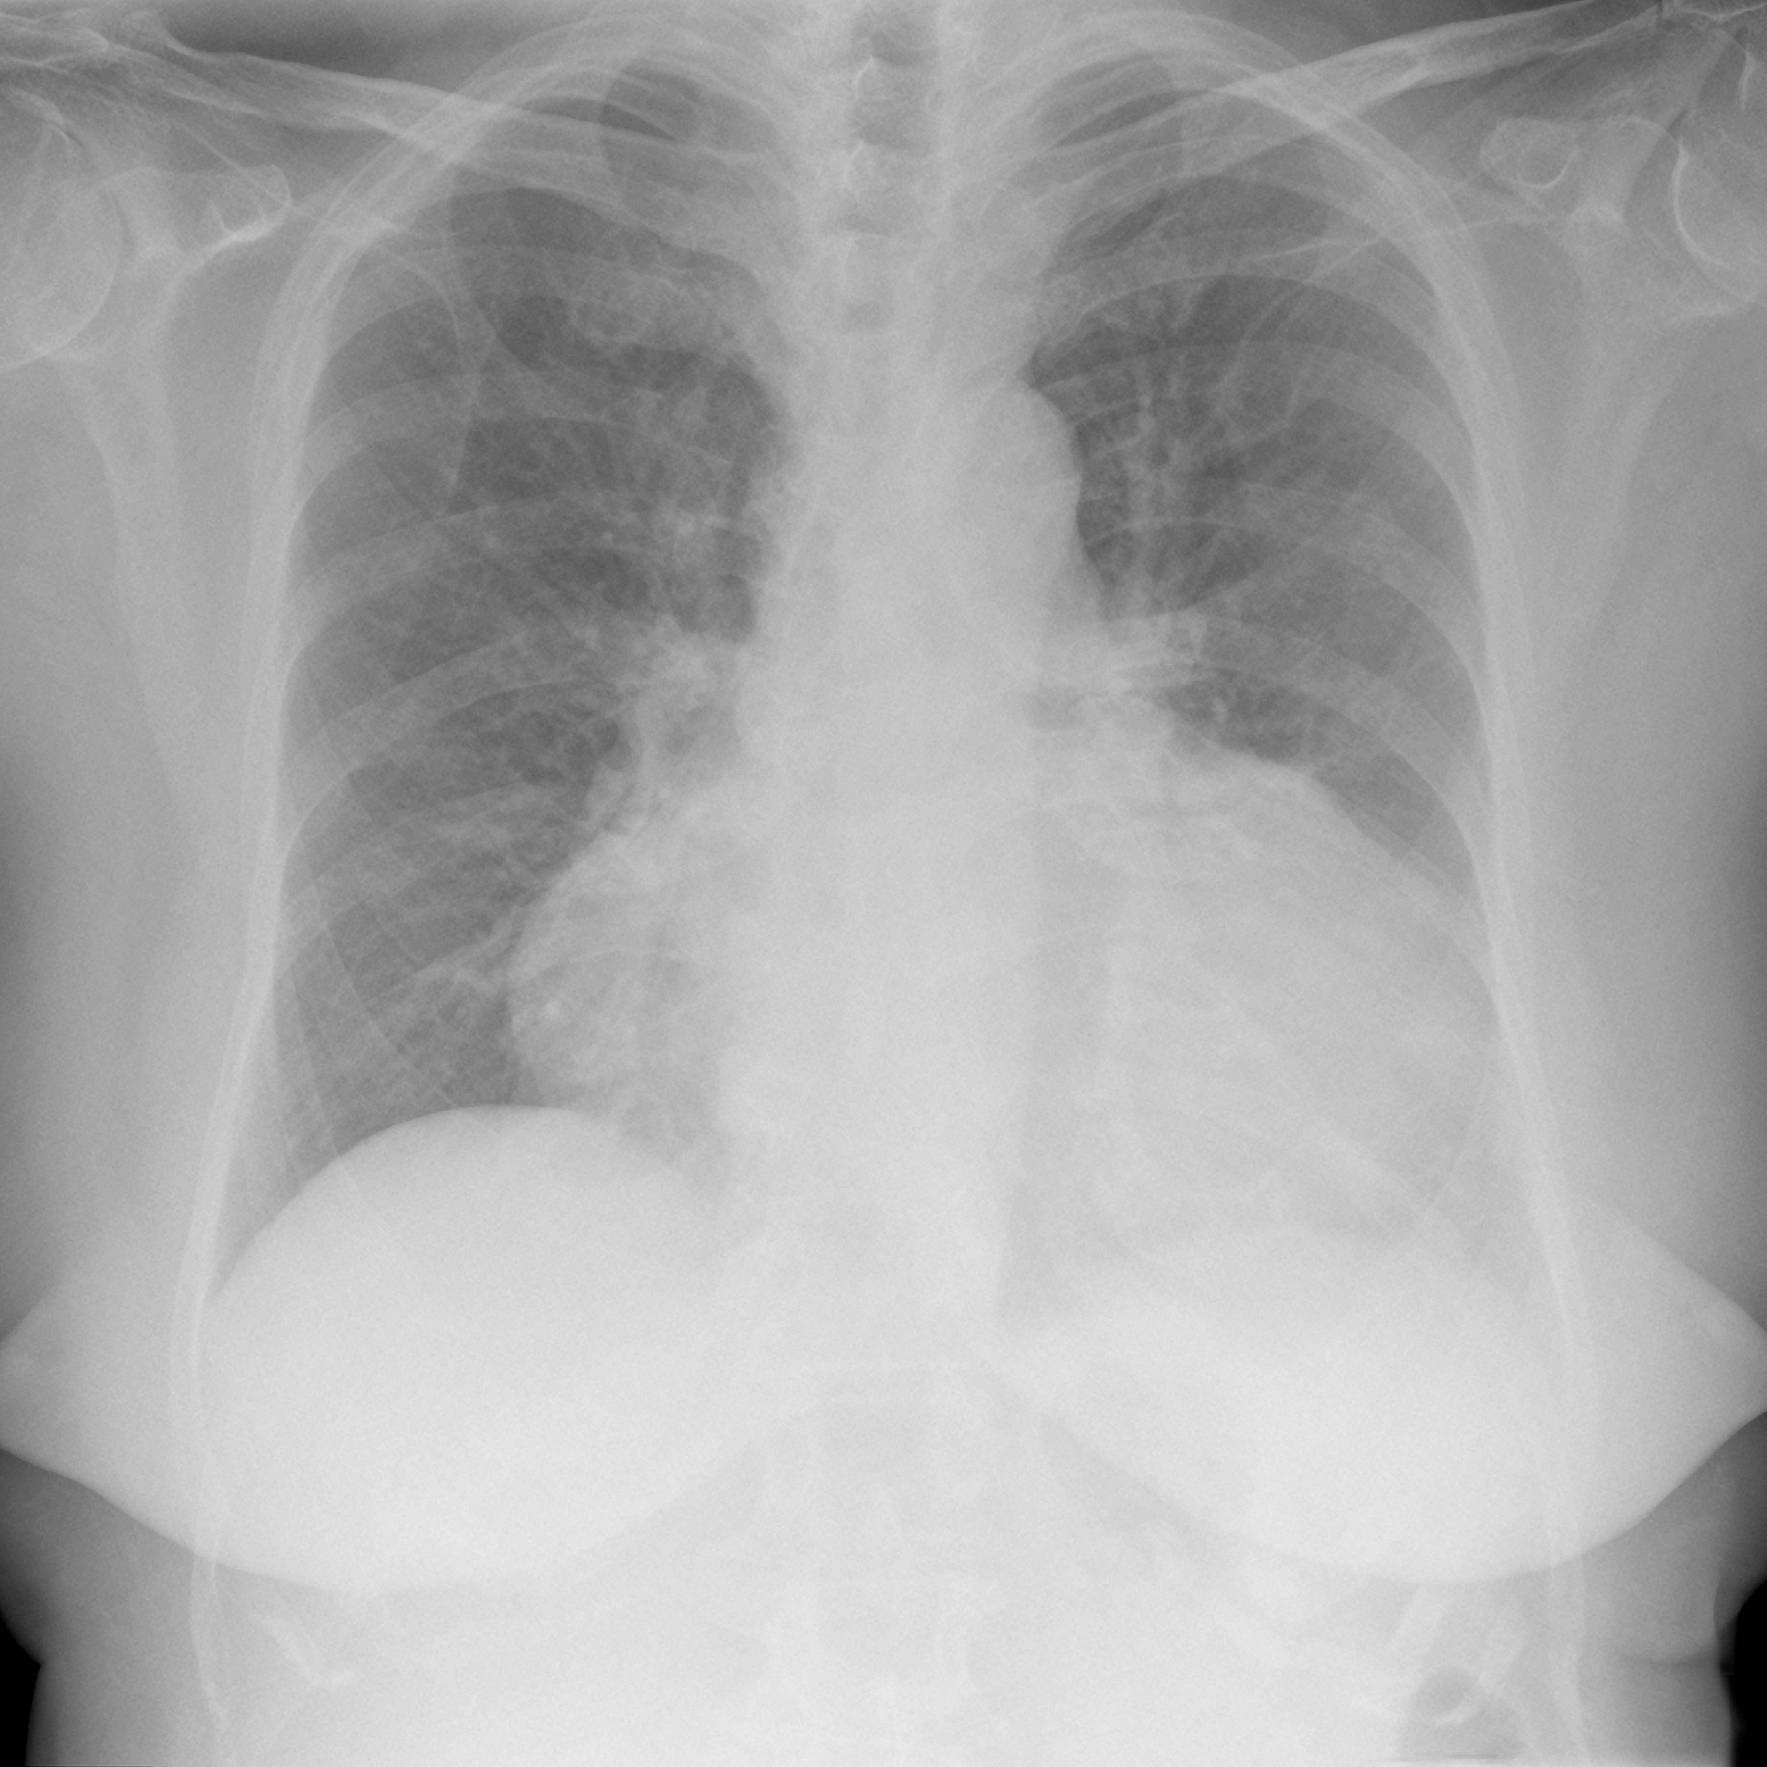

心衰的指标通常是通过测量心房利钠肽前体(NT-proBNP)的水平来确定的。NT-proBNP是一种由心脏产生的激素,其水平可以反映心脏扩张和心肌受损的程度。正常情况下,NT-proBNP的水平较低,通常在0-125 pg/mL范围内。然而,心衰患者的NT-proBNP水平通常会升高,且高于1000 pg/mL,以提示心衰的可能性。需要注意的是,心衰的确诊不能仅仅依靠NT-proBNP水平,还需要综合考虑患者的症状、体征和其他相关检查结果。因此,如果您怀疑自己或他人可能患有心衰,请务必咨询医生进行确诊和治疗。

NT-proBNP水平超过1000pg/mL提示心衰风险